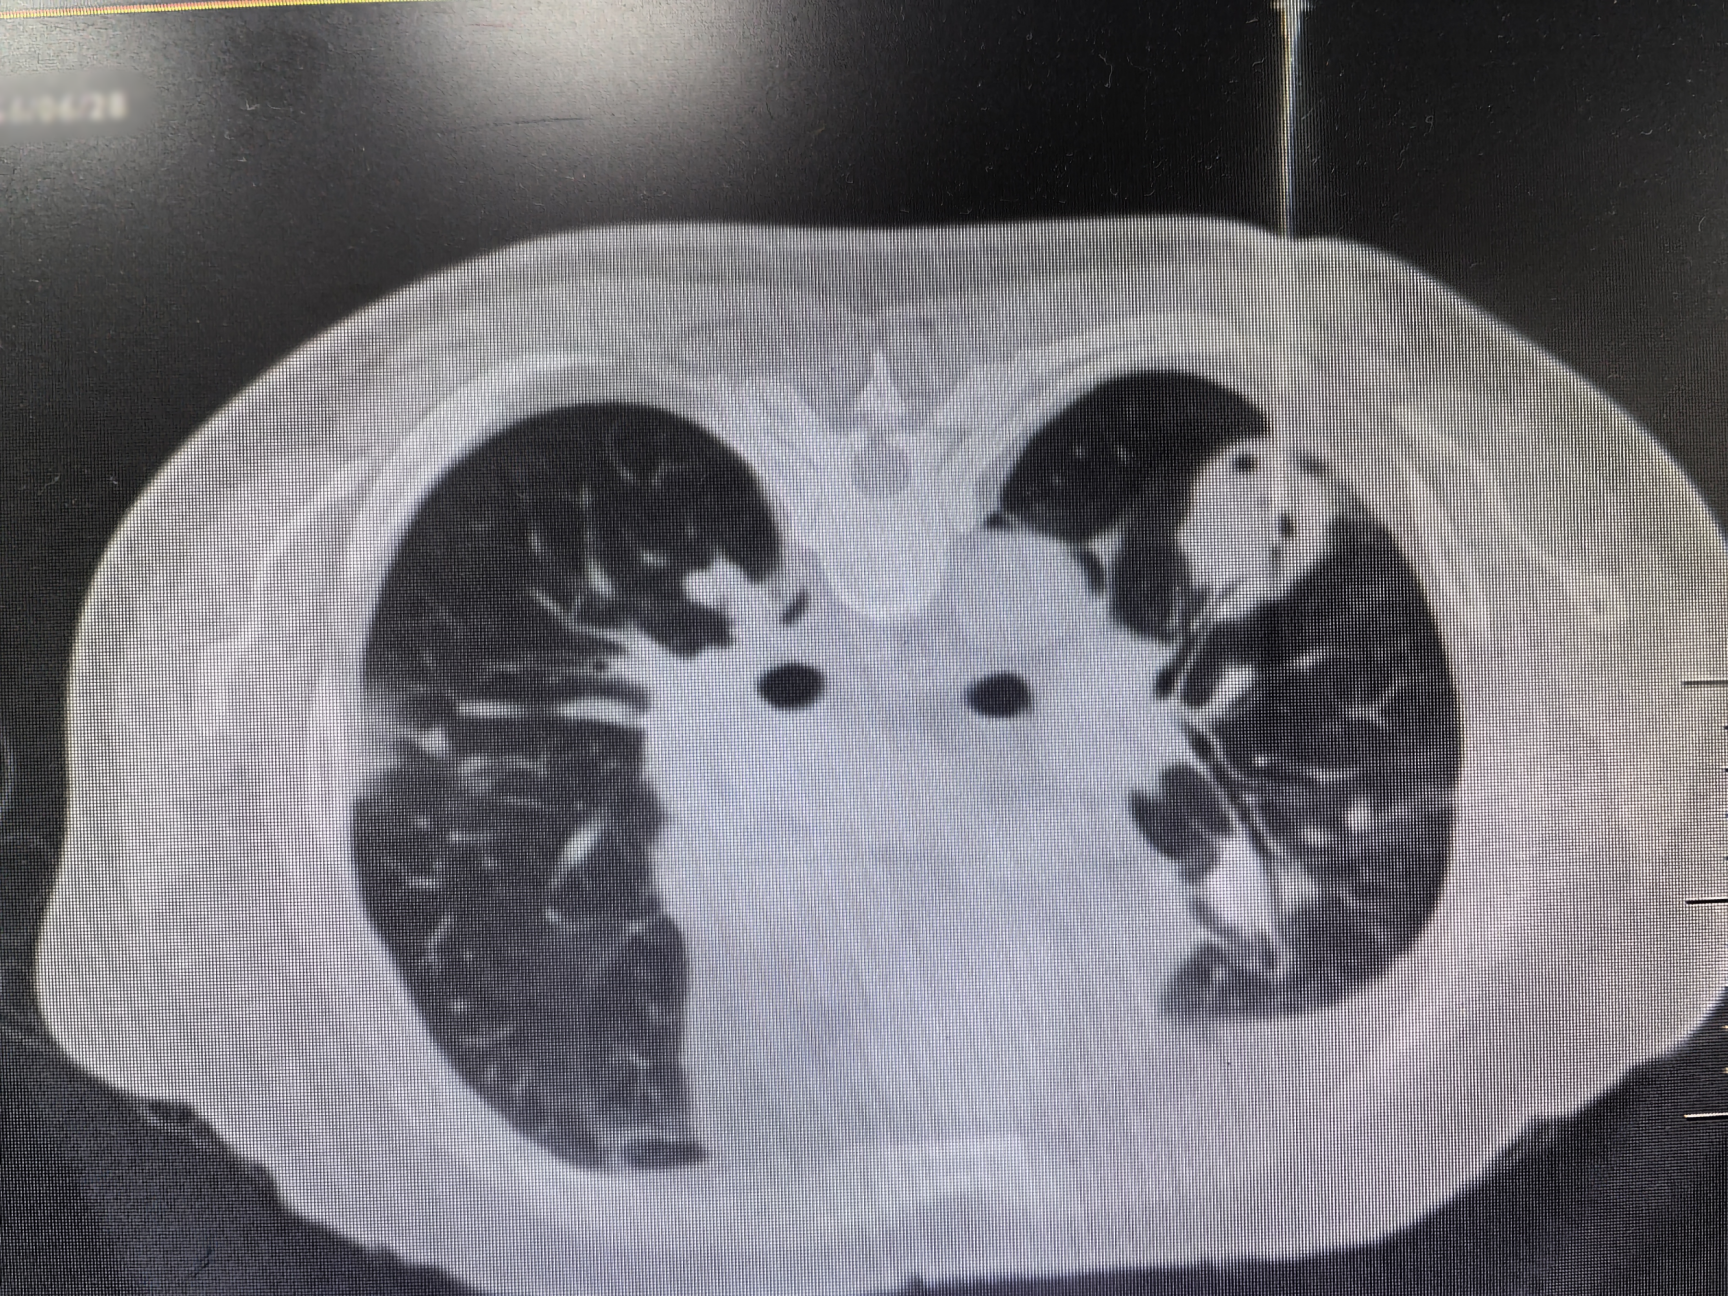

该患者因进行性加重的咳嗽、胸闷、气促,辗转多家医院,进行了多次临床检查及肺结节穿刺活检,均未能明确诊断。患者一度焦虑地表示欲前往广州请钟南山院士诊治。柴燕玲教授接诊后,与科室陆霓虹博士等专家进行了讨论,初步怀疑为罕见的血管炎性疾病-韦格纳肉芽肿病(Wegener’s granulomatosis,WG),其确诊依赖肺活检。

与患者反复沟通病情后,患者最终同意再次进行肺活检。完善术前检查、排除肺活检禁忌证后,在呼吸介入团队医护配合下,陆霓虹博士为患者实施了高难度“双肺结节同步穿刺活检术”。手术仅用时12分钟,顺利获取病变组织,且患者无并发症。病理检查(ROSE)提示肉芽肿性病变,结合血液c-ANCA阳性,最终确诊为“韦格纳肉芽肿病”(WG)。经对症治疗,患者症状显著好转。

韦格纳肉芽肿病(WG)是一种特殊的坏死性肉芽肿性血管炎,病因不明。病变常累及多个器官,病理表现为肉芽肿性病变,伴血管壁炎症。因WG发病率较低,肺部病变常常被误诊为肺部肿瘤或者肺结核。2024年发表的中国肺结节规范化诊疗专家共识指出,双肺多发结节须进行双肺的活检取材,避免结节漏诊及误诊。双肺同步穿刺技术难度较高,对操作医师的熟练程度、操作技术水平均有要求。